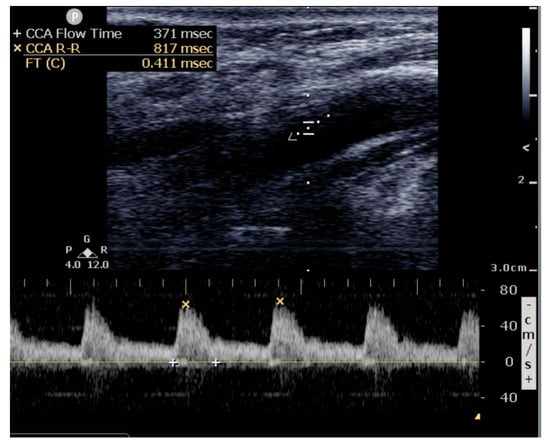

- 7 msec increase in corrected flow time (FTc) after fluid challenge.